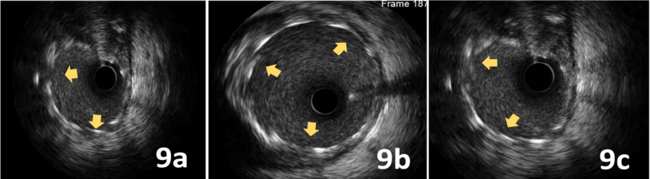

Final IVUS showed adequate expansion and no edge dissections (Figure 9). The final angiographic result is shown in Figure 10. There were no complications at all during the procedure, and the patient was discharged 3 days later.